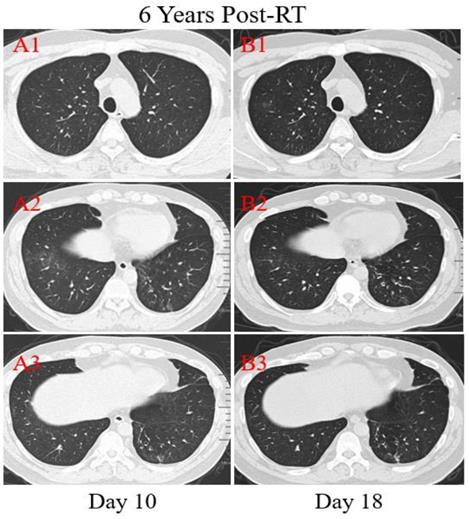

Figure 5

Transverse unenhanced thin-section serial CT scans from a 39-year-old male with COVID-19 pneumonia. Chest CT images on the 10th day after symptom onset demonstrated multiple ground-glass opacities of the lower lobes of both lungs peripherally (A2), and a few linear opacities in upper lobe lower lingual segment of the left lung (A3). Follow-up CT at the 18th day demonstrated significant improvement in the extent and density of the ground-glass opacities (B2), and appearance of new focal ground-glass opacities of the upper lobe of right lung (B1).

Patient 4: A 39-year-old male was diagnosed with nasopharyngeal carcinoma (T2N2M0) treated with radical concurrent chemoradiotherapy in June 2013. He was admitted to the hospital with a positive result of the swab nucleic acid test for COVID-19 on February 14, 2020. The patient had transient diarrhea 10 days ago but no other symptoms afterward. The patient traveled to Zhuhai from the infected area (Wuhan, China) and had close contact with the confirmed COVID-19 patient, his aunt. At admission, both lungs were clear on auscultation. Laboratory studies showed normal blood routine results. Reslus of influenza A and B antigen screening for this patient were negative. The T lymphocyte subsets test showed a slight drop in CD4+ and CD8+ T cell counts. Chest CT images were obtained on the 10th day after symptom onset and showed that there were multiple ground-glass opacities of the lower lobes of both lungs peripherally and subpleurally (Figure 5. A2). A few linear opacities were presented in upper lobe lower lingual segment of the left lung (Figure 5. A3) within the ionizing radiation area, indicating radiation fibrosis. After 8 days of anti-viral therapy with resochin and supportive treatment, follow-up CT scans demonstrated a significant improvement in the extent and density of the ground-glass opacities (Figure 5. B2), but found a new focal ground-glass opacity (GGO) in the upper lobe of right lung (Figure 5. A1, B1). Treatment continued until the result of the swab test became negative.